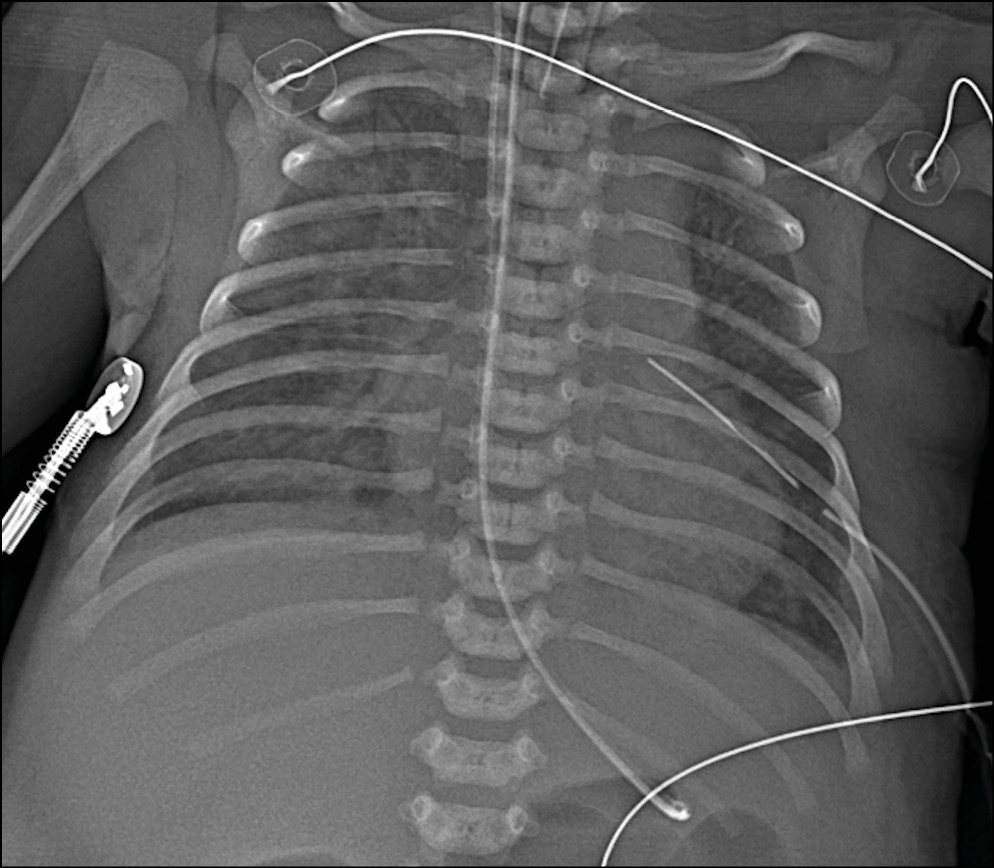

Рентгенография органов грудной клетки традиционно является наиболее важной в оценке легочной паренхимы у детей раннего возраста: зачастую лечащие врачи назначают выполнение торакоабдоминальной рентгенограммы для одномоментного исследования органов грудной и брюшной полости. Наиболее важной задачей при исследовании органов грудной клетки является непосредственно оценка паренхимы легких, ее пневматизация и наличие участков затенения. Необходимо отметить изменения со стороны легочного рисунка — усиление, сгущение, деформацию или его обеднение. Необходимо оценить уровень положения диафрагмы и состояние реберно-диафрагмальных синусов, а также положение зондов, дренажей и катетеров (рис. 2).

Рис. 2. Пациент с коарктацией аорты. Снимок выполнен на третьи сутки жизни. Исследование выполнено при помощи микрофокусного рентгеновского аппарата.

Fig. 2. Patient with aortal coarctation, 3 day of life. Microfocus X-ray device.